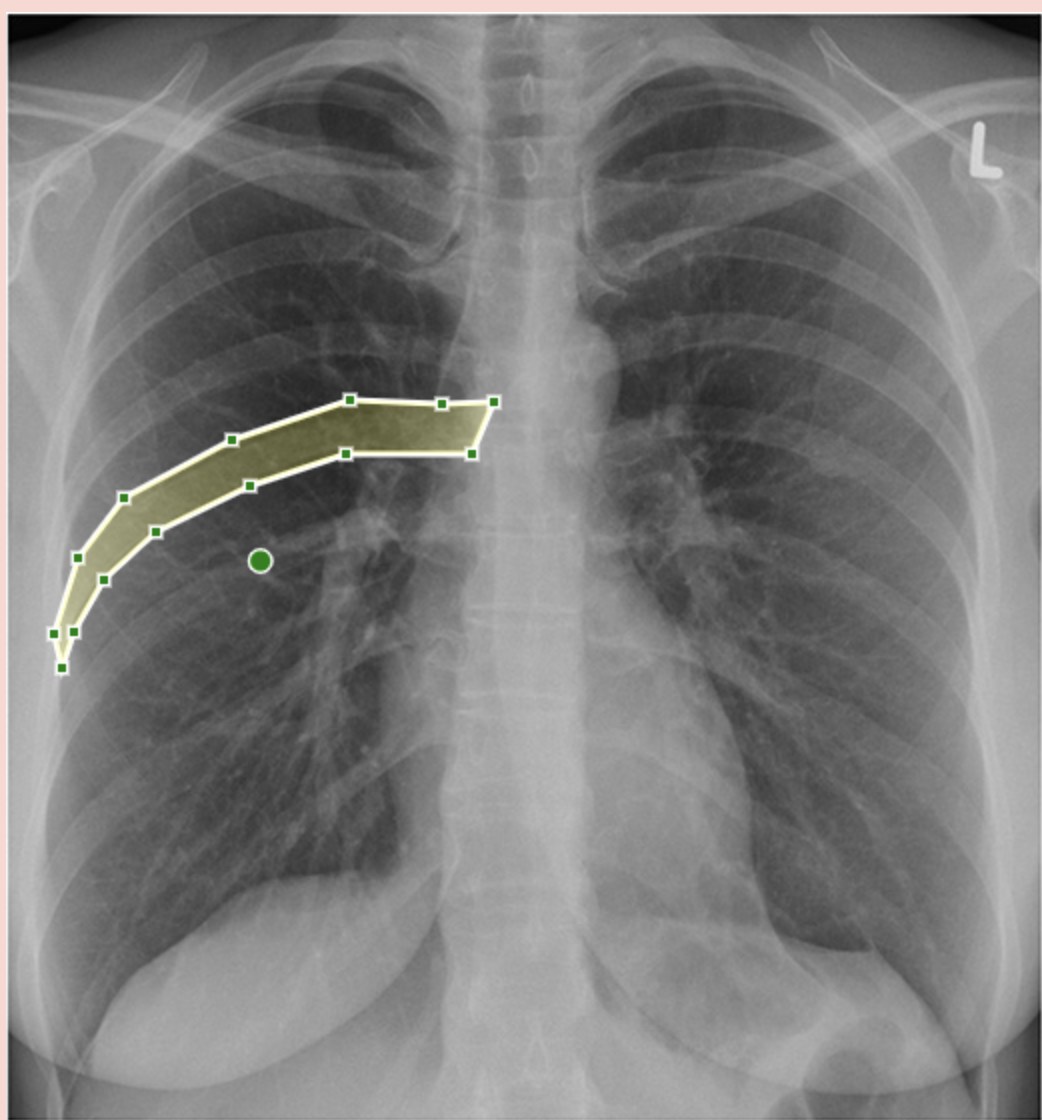

What is being shown here?

A

Right hemidiaphragm